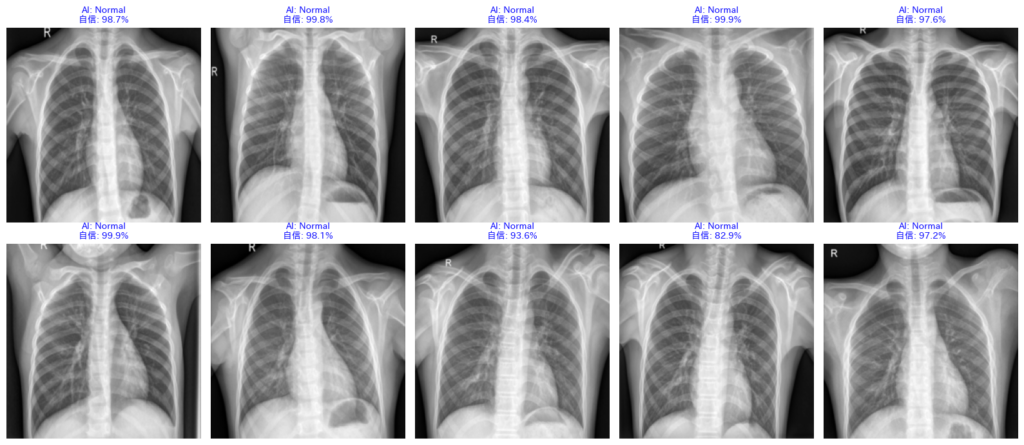

4. 結果の読み解き方:AIドクターの「カルテ」を査読する

コードの実行、お疲れ様でした。画面には、AIが診断した10枚のレントゲン画像が表示されているはずです。

これは単なる画像一覧ではありません。AIドクターがあなたに提出してきた「診断レポート(カルテ)」です。

指導医であるあなたは、このレポートを厳しくチェックし、AIの実力を評価しなければなりません。

どこに注目すべきか、そのポイントを「症例検討会」のつもりで見ていきましょう。

① AIの「自信」を読む(確信度)

画像の上の文字を見てください。例えば、以下のように書かれています。

AI: Pneumonia (99.8%)

これは、「99.8%の確率で肺炎だと思います」というAIの主張です。

この数字は、AIの脳内で行われた計算結果(ソフトマックス関数からの出力)そのものです。

- 高い数値(90%以上):AIは非常に強い根拠を持って診断しています。「典型的な肺炎の影がある」と判断した状態です。

- 低い数値(50〜60%):AIも迷っています。「肺炎っぽい気もするけど、正常かもしれない…」という、境界領域の症例です。

臨床現場では、この数値が「AIの自信の無さ」を知る手がかりになります。